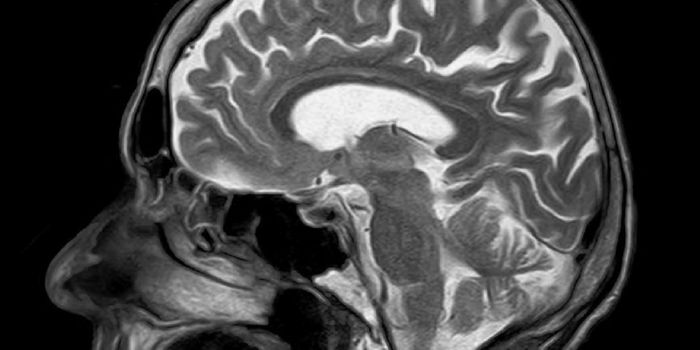

Read the latest articles about newly released neuroscience research and advances in experimental techniques. Topics include research news in neuroscience, neurology, psychology, brain science and cognitive sciences.